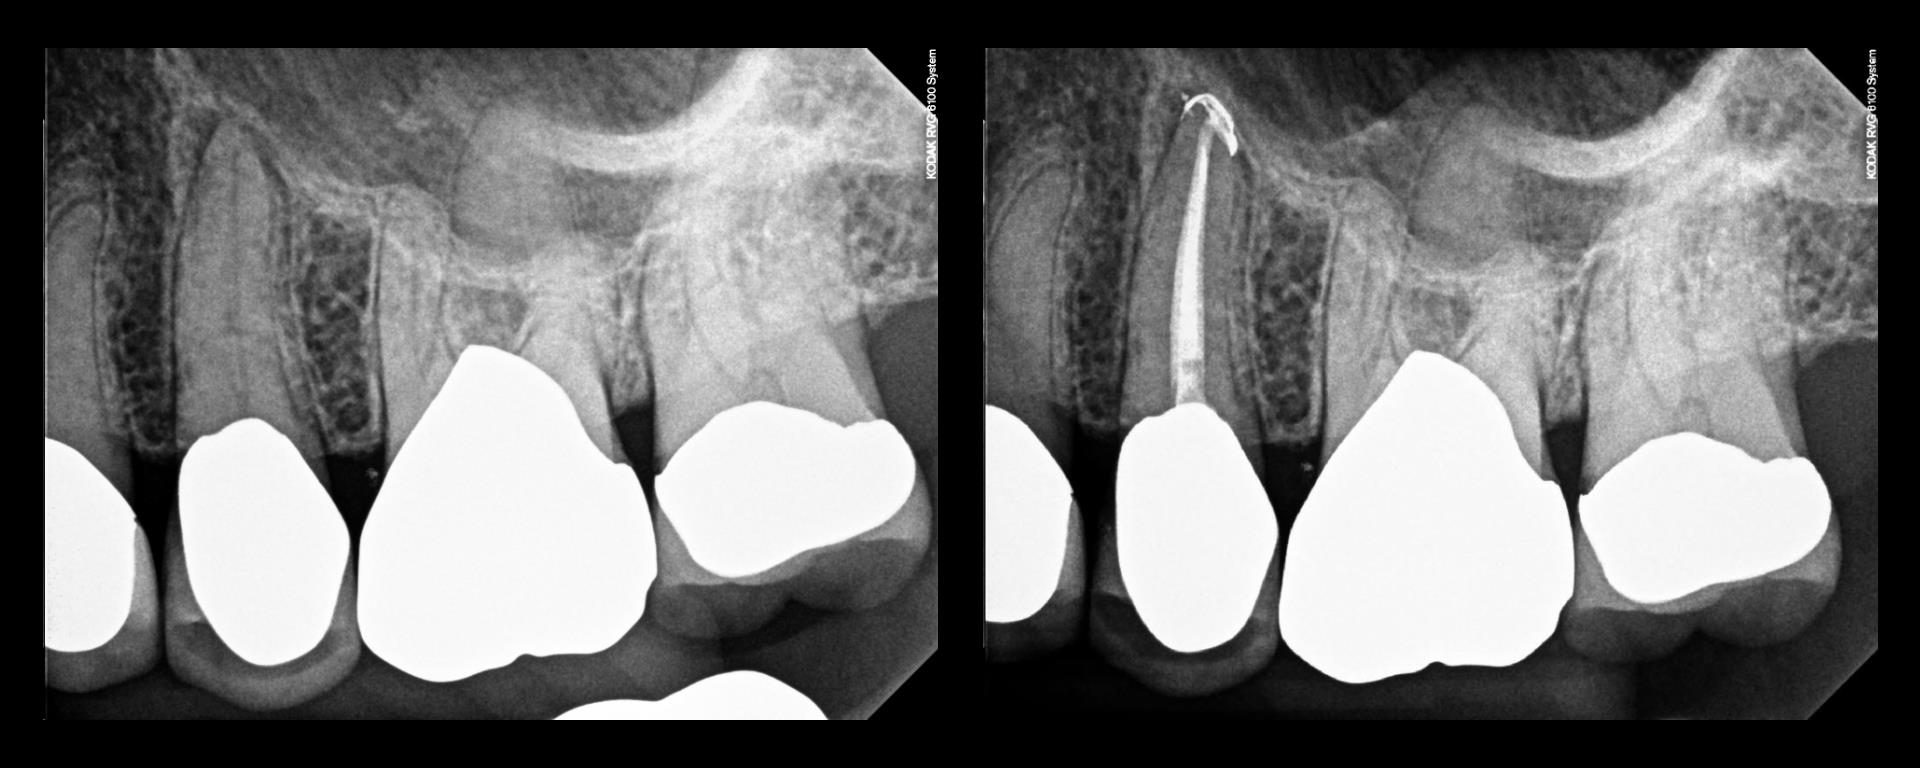

Sat emergency

Poor Joy…..having to come in on her birthday… Patient here from Russia for treatment of ALS–in a wheelchair. Daughter a patient of mine—lead scientist on the MARS probe at Cal Tech. Just wants to be functional and to minimize costs if possible. Patient is 78. Tried to talk about a 6-12 implant supported bridge…..no go. […]